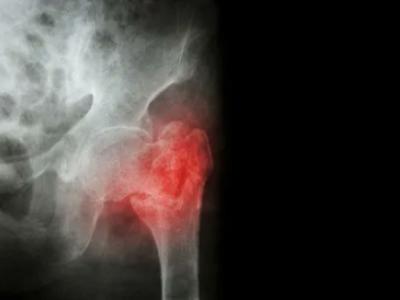

Fat and bone are never alone: osteoporotic fracture in RA Dr. David Liew discusses Abstract 889 at #ACR22. Abstract 88

Fat and bone are never alone: osteoporotic fracture in RA Dr. David Liew discusses Abstract 889 at #ACR22. Abstract 889: Serum Adipokines Predict Incident Osteoporotic Fracture in Patients with Rheumatoid Arthritis https://t.co/4IrdQBq1z2 https://t.co/2HySVG1SGY